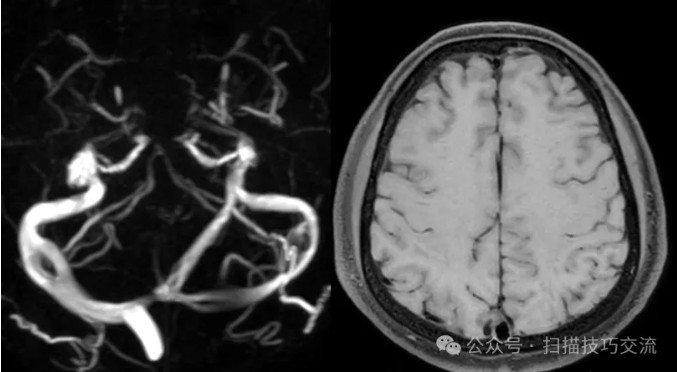

临床申请:颅脑平扫,静脉成像,磁敏感成像,颅内静脉血管黑血成像。

静脉有扩张,无血栓。